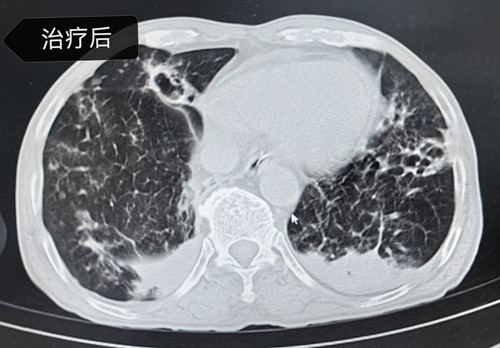

科室主任李建民带领团队立即为姚大爷在科内组织疑难病例讨论,经过仔细询问病史及分析病情。经肺泡灌洗液的病原学检查,在其肺内找到了烟曲霉菌(真菌的一种)、肺炎链球菌(社区获得性肺炎的常见细菌)等病原体混合感染,通过积极的抗真菌、抗细菌、抗炎症反应、俯卧位等综合治疗,姚大爷最终转危为安,经过一段时间治疗,2月5日,姚大爷身体达到出院条件,待雨雪冰冻天气情况好转后返乡过年。